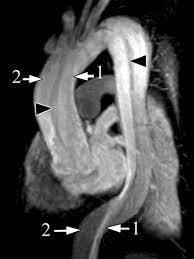

What happens is a tear in the tunica intima of the aorta forms and the high-pressured blood flowing through the aorta begins to tunnel between the tunica intima in the tunica media separating the two layers, now as the high-pressured blood continues to shear more and more of the tunica intima of the tunica media blood starts to pull between the two layers increasing the outside diameter of the blood vessel the area where blood collects between the tunica intima and the media is called a false lumen and the true lumen is the regular lumen of the blood vessel since high pressure is a cause of aortic dissection.

An aortic dissection is an emergency because it can lead to hypotension or low blood pressure as well as a shock if there's a rupture and significant blood loss on a chest x-ray there's typically a widened aorta more sensitive imaging techniques that are commonly used include a trans-esophageal echocardiogram which is where an ultrasound probe is passed through the esophagus to obtain a clear picture of the aorta there's also ct angiography and magnetic resonance angiography both of which look closely at the blood vessels. An aortic dissection needs to be treated immediately type A aortic dissections are treated surgically where a surgeon takes out as much of the dissected aorta as possible and blocks the entry of blood into the wall of the aorta the aortic wall is then reconstructed with synthetic graft and sometimes that graft is propped open with a wire mesh stent. Type B aortic dissections are treated with beta blockers and nitroprusside.